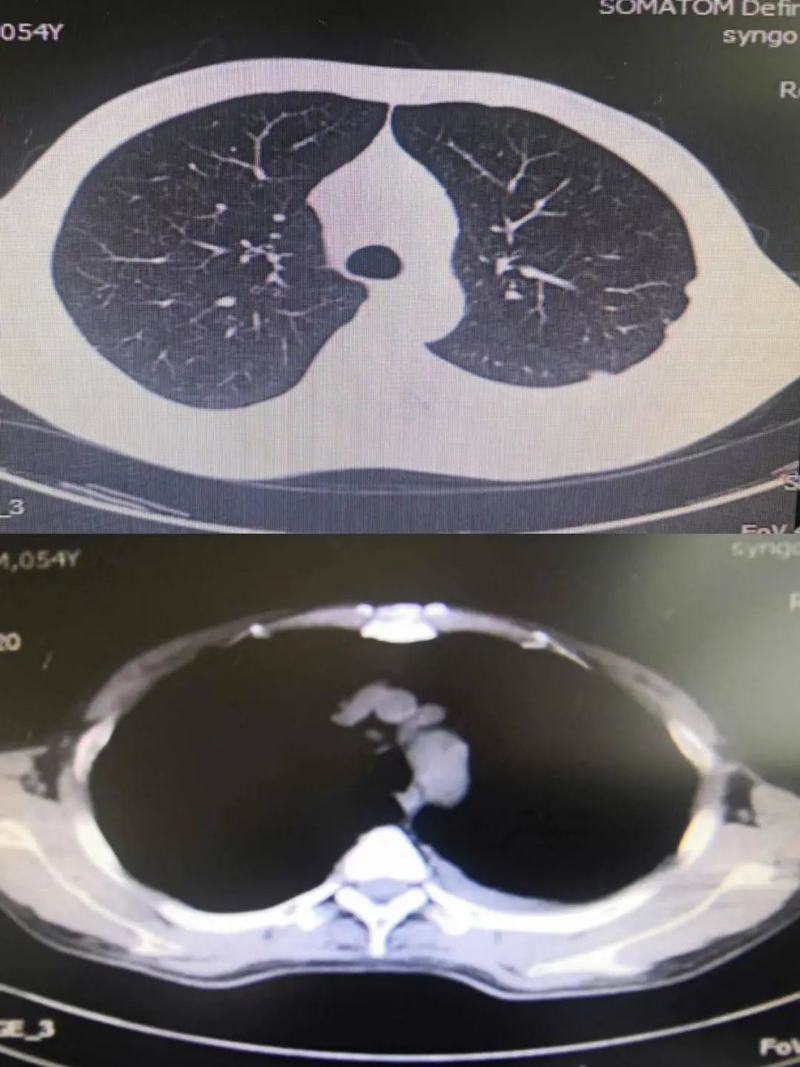

近日,兰州市第二人民医院呼吸科收治了一名中年男性患者,主因“头晕、头痛10余年,加重1周”入院。入院后行肺部CT:双肺多发结节,考虑炎性、增殖灶,左侧胸腔及叶间少量积液,左侧胸膜明显增厚,胸膜间皮瘤不除外。

由于患者肺部无较大的可及性实体病灶,无法行支气管镜以及肺穿刺活检进行确诊。这给临床带来了很大的挑战。科主任贺思云主任详细阅片并病情评估患者病情后,考虑:胸腔镜为患者首选的诊疗手段,需尽快行胸腔镜明确诊断。

但患者胸腔积液非常少,胸腔镜操作难度大,风险高,术前贺思云主任和相关医护人员做了充分的评估和准备。术中发现壁层以及脏层胸膜弥漫性白色结节,镜下直视下成功取多块活检送病理检查。

我科已经对此技术熟练掌握并灵活应用。随后病理结果汇报,确诊为:晚期肺腺癌,科主任贺思云主任及时为患者制定了个体化的化疗等治疗方案,患者目前病情平稳已出院。